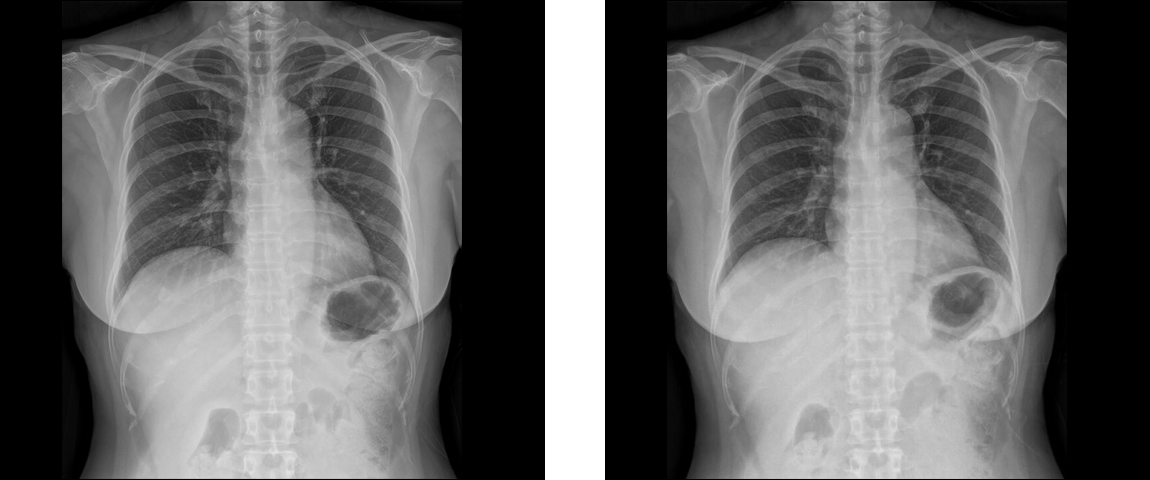

Können Sie einen Unterschied erkennen?

Thorax PA  (120 kVp / 1.68 mAs / 16.7 μSv / BMI 25.6) Thorax PA (120 kVp / 0.82 mAs / 8.05 μSv / BMI 25.6)

Thorax PA Vergleichsaufnahmen (Links: 120 kVp / 1.68 mAs / 16.7 μSv / BMI 25.6, Rechts: 120 kVp / 0.82 mAs / 8.05 μSv / BMI 25.6)